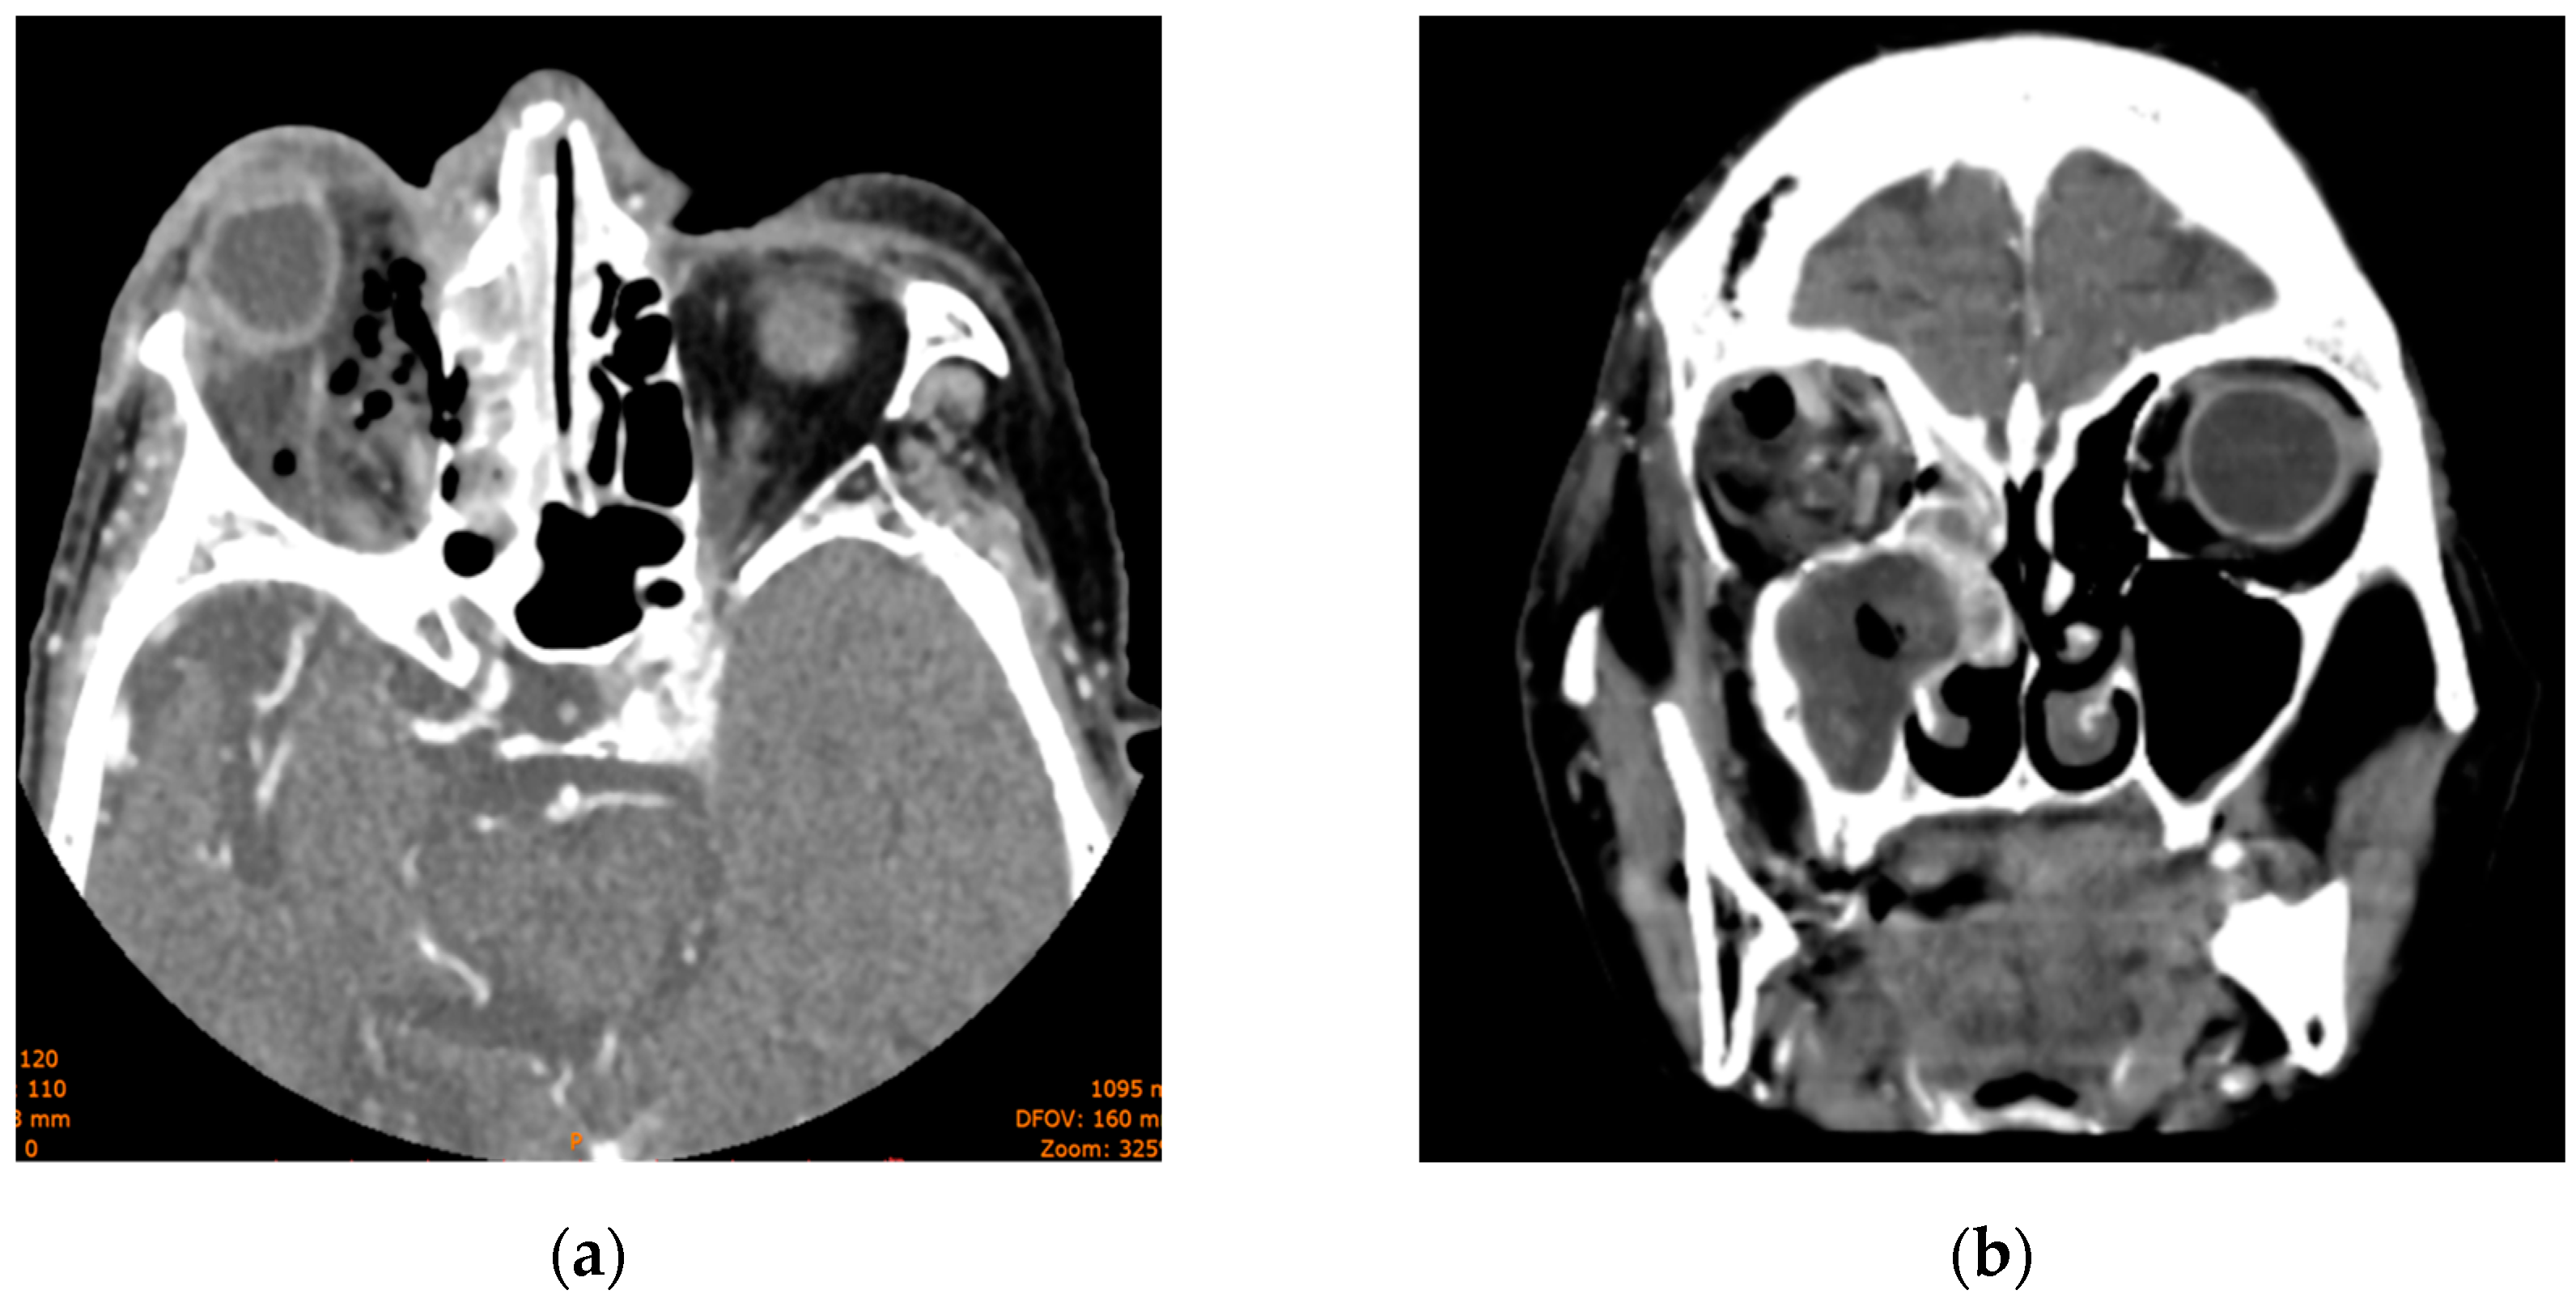

The head CT revealed right-sided orbital abscess with reticulation of the fat, pansinusitis with maxillary and ethmoid sinus opacification (Figure 2), multiple gas bubbles extending from the ethmoidal cells to the right orbit, a stretched right optic nerve, and posterior globe tenting (Figure 3). The abscess in the right canine space originated from the buccal roots of teeth 13 and 15. The fluid collection extended continuously from the right canine space upward and backward to the right lateral orbit.

Figure 3. Computed tomography scan displaying maxillary and ethmoid sinus opacification, multiple gas bubbles extending from the ethmoidal cells to the right orbit, a stretched right optic nerve, and posterior globe tenting: (a) axial section; (b) coronal section.